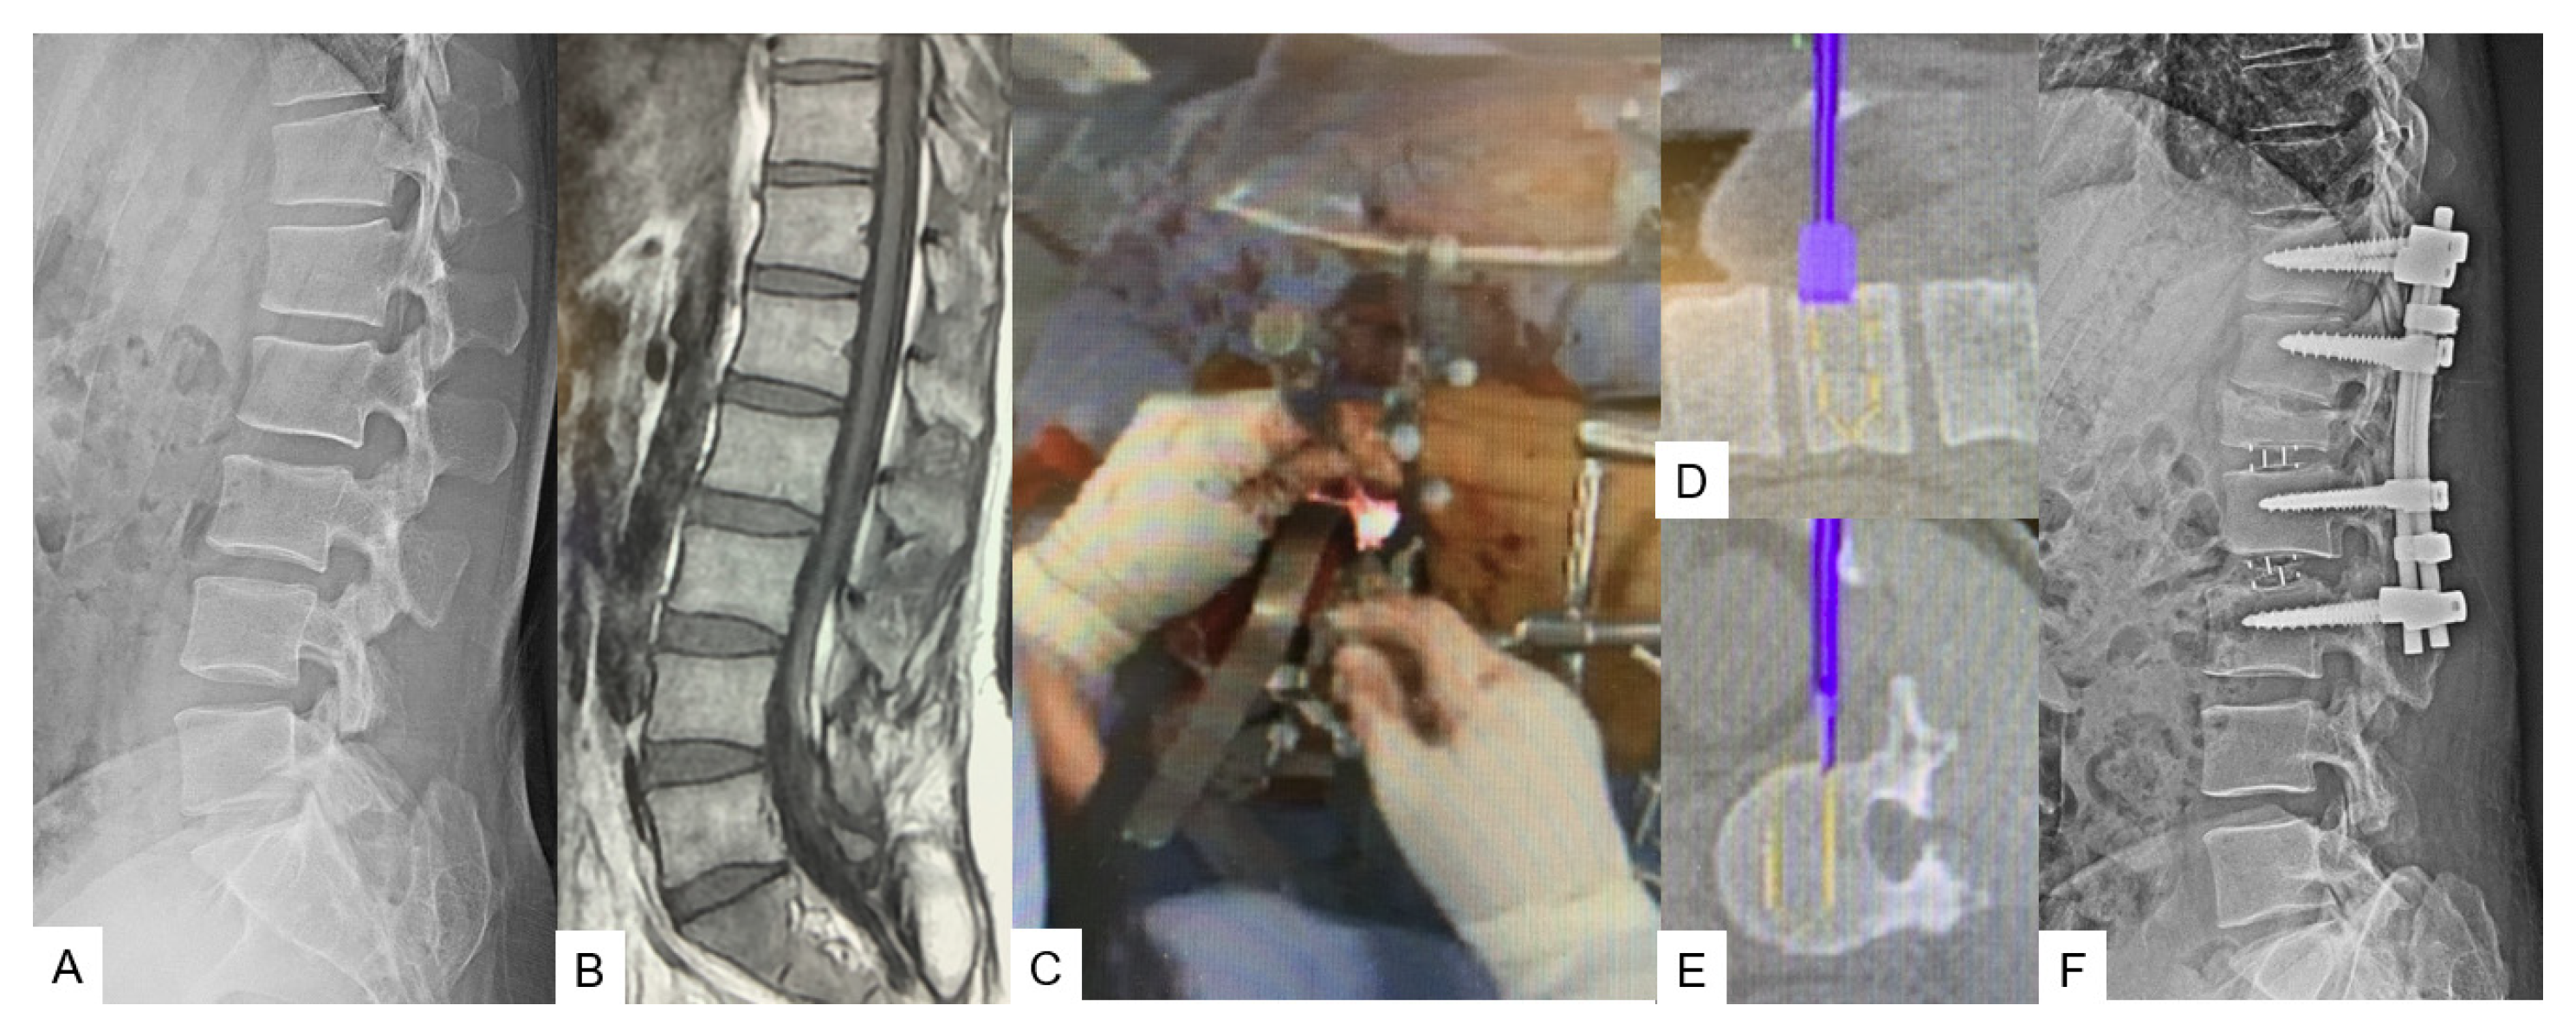

3.1.1. OLIF51 [10]

3.1.2. Lateral Osteotomy [11]